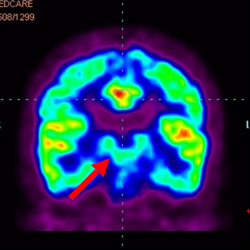

細胞治療后,藍色和黑色區域減少,并且看到更活躍的區域。這表明損傷減少并改善了大腦功能。

細胞治療前 PET CT 掃描顯示神經組織中的藍/黑色區域,表明腦癱引起的大腦損傷。

這證明細胞療法是治療腦癱兒童安全有效的方法。細胞療法可以更新大腦損傷的核心,并且可以通過 PET CT 掃描來監測大腦的改善情況。這些細胞療法與標準治療一起促進腦癱兒童的生長和改善。